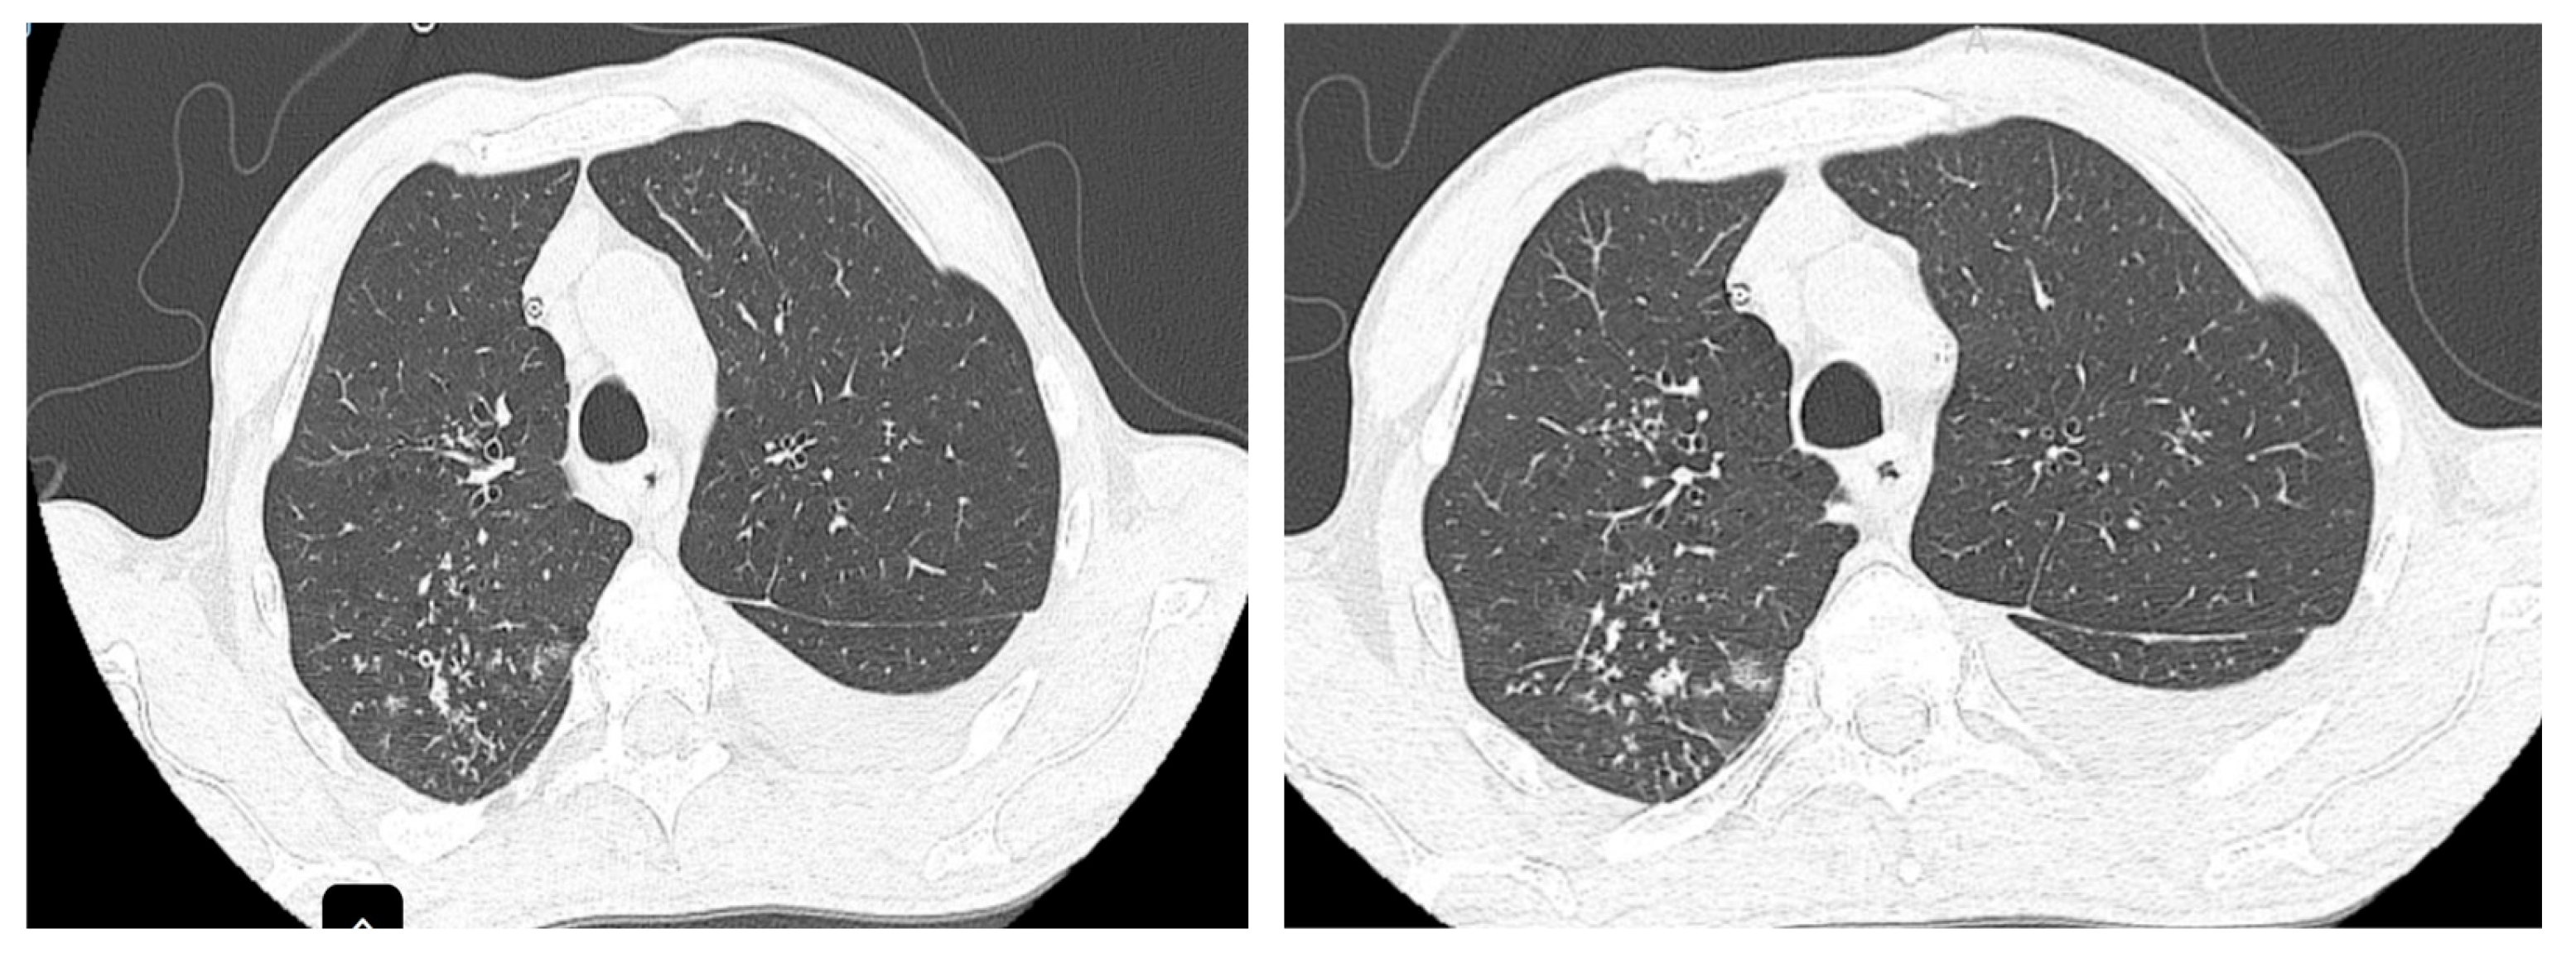

The patient was referred to the pulmonology department following combined imaging exploration (computed tomography—CT; positron emission tomography—PET) which revealed multiple pulmonary micro- and macronodular lesions with diffuse contours, located in the segments of both upper lobes and the right Fowler segment, with varying degrees of metabolic activity (Figure 1). Additionally, a flat, moderately enhancing lesion was located on the left lateral pleura, along with left pleurisy. There were also flat, metabolically active lesions at the level of the inner surface of the diaphragmatic domes and large-volume ascites.

Figure 1. Metabolic activity in the posterior segment of the right upper lobe (RUL).